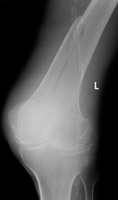

- Click on the image for a larger versionBLateral radiograph of the distal femur.